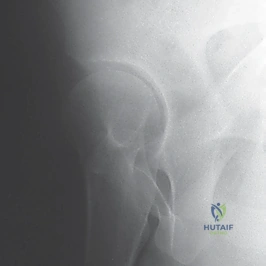

صور إضافية لخطوات الجراحة الدقيقة والمتابعة الإشعاعية

يوثق الأستاذ الدكتور محمد هطيف كل خطوة جراحية لضمان أعلى معايير الجودة والشفافية الطبية.